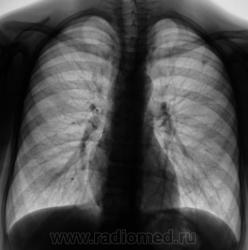

При расшифровке флюорограмм "взят на контроль". Подросток, первичная постановка на военный учёт. Жалоб нет.

Первая флюорограмма. Конечно, взяли на контроль. Разрезали. Сейчас выложу томограммы. Томограммы, как и всегда с "букетом роз".

А рентгенологически, что выставлять? Очаговый?

Два сегмента очаговый, больше двух диссеминир.

Возможно, Вы правы. Но мы выставили очаговый. Записали изображение на диск в цифровом формате, фтизиатры забрали себе.